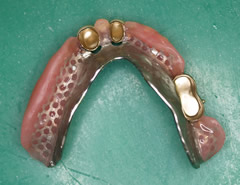

症例 4

鳥取県 53才 男性

入れ歯の相談例を記載します。

私は現在53才の男性ですが、下顎(したあご)には歯が3本しかなく困っています。

※注釈 この方の上歯は全部自分の歯でした。こういった上顎が自分の歯の場合は、下顎に負担が掛かり、通常の作り方では上手くいかないことが多いのです、コーヌスで治療しました。